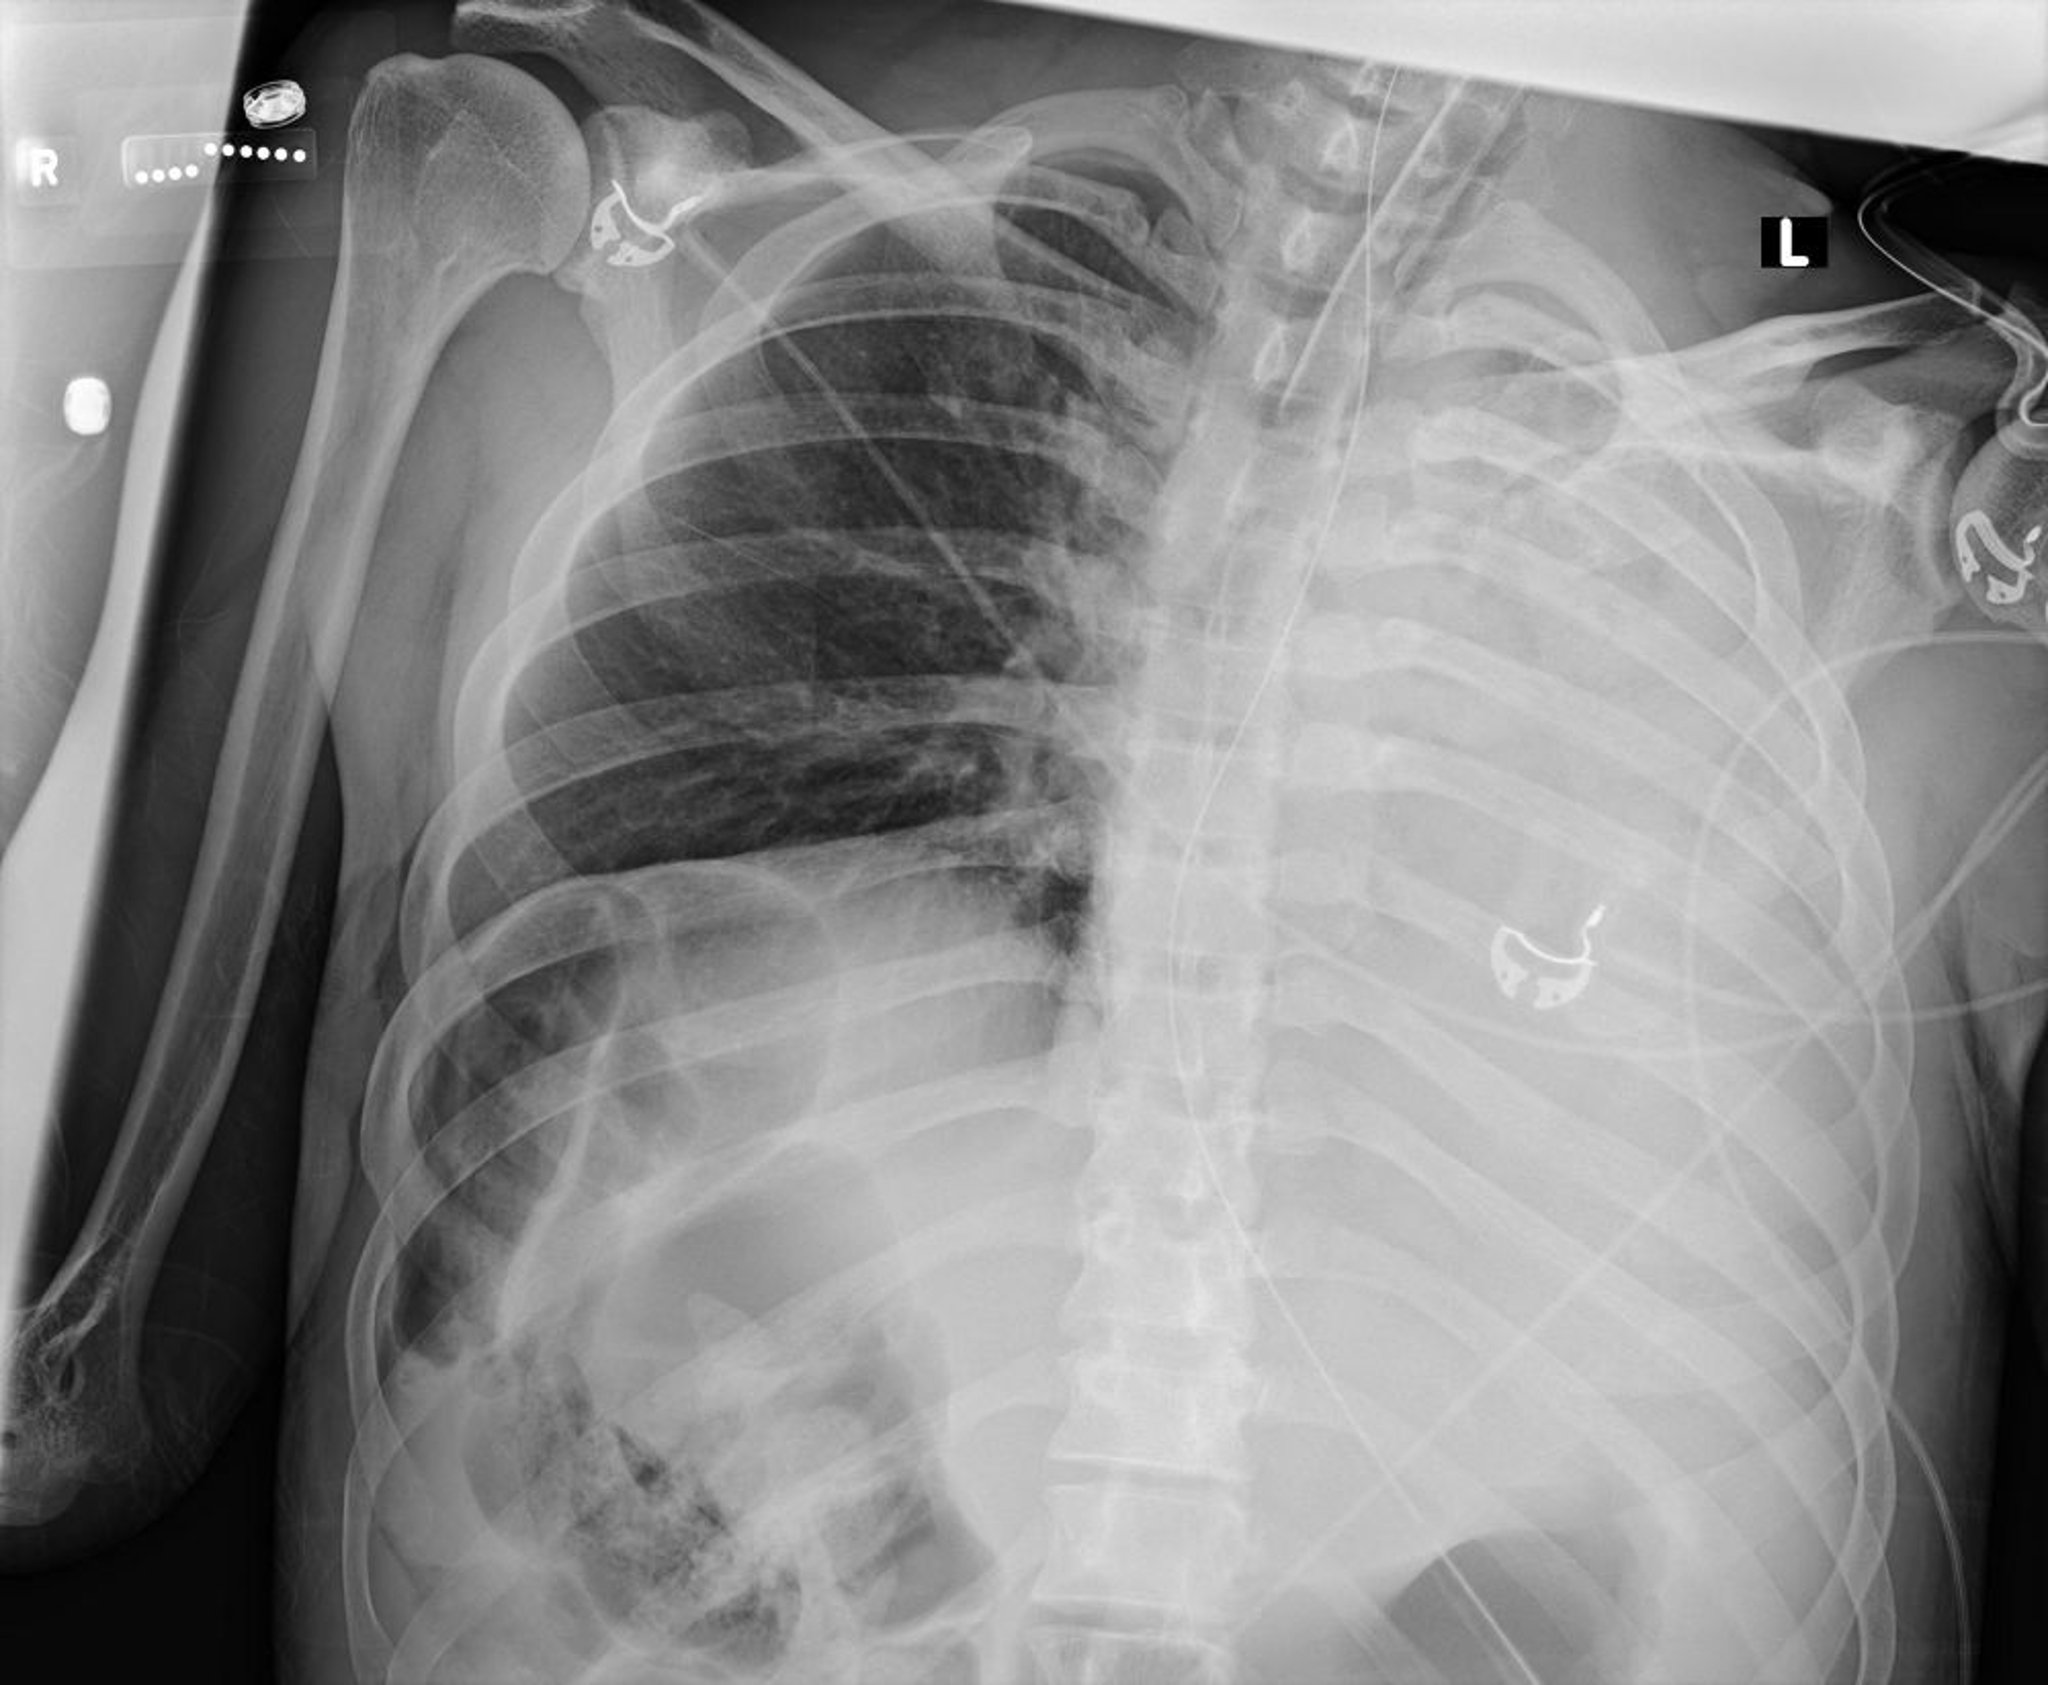

Atelectasia y colapso del pulmón izquierdo (radiografía)

Esta radiografía de tórax muestra el colapso de todos los lóbulos del pulmón izquierdo debido a un tapón de moco.